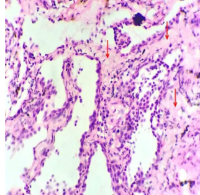

Cryptogenic Organizing Pneumonia: A Misdiagnosis or Missed Diagnosis in Resource –Poor Settings: A Case Report and Literature Review.

Obidinma-Igwe, Avwerosuoghene Progress, Obiefuna Adaobi, Nwosu Nnamdi, Nlewedim Paul Augustine, Udeh Chukwuemeka Frankline, Odinaka Chinwe, Agu Felix, Onyedum Cajetan Chigozie, Chukwuka Chinwe (Author)

27-31